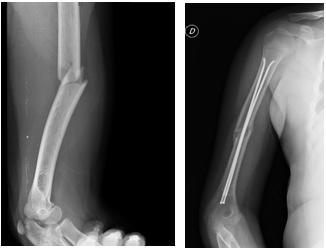

Fratture della diafisi femorale

L'evoluzione e il trattamento di queste fratture sono condizionati dalle peculiarità anatomiche e fisiologiche dell'osso infantile. La presenza delle placche coniugali e la conseguente necessità di non danneggiarle può limitare le possibilità terapeutiche.

Lo spiccato potere osteogenico favorisce la costante e rapida consolidazione: le pseudoartrosi sono rare e quasi sempre iatrogene. Anche le rigidità articolari sono infrequenti. Turbe dell'accrescimento sono possibili sia in difetto (per concomitante lesione della cartilagine di accrescimento ad esempio in distacco epifisario tipo Salter V) che in eccesso (iperllaungamento post-traumatico). Particolamente frequente è l'allungamento, probabimente dovuto al fatto che nelle fratture diafisarie l'iperemia locale conseguente ai processi riparativi si ripercuote sulle placche coniugali vicine che vengono stimolate per incremento dei processi metabolici.

L'entità dell'allungamento varia a seconda della sede, età, tipo di frattura, delle manovre più o meno complesse messe in atto per ottenere la riduzione (gypsotomie, riduzioni ripetute) ed delle tecniche chirurgiche (maggiore accentuazione della ipemetria in caso di esteso scollamento periostale e nell'utilizzo di placche).

L'autocorreggibilità dei mal-allinementi post-fratturativi nell'età pediatrica è un fenomeno ben conosciuto in traumatologia infantile. In linea di massima nei pazienti più piccoli sono tollerabili fino a 20-25° di angolazione sui due piani ortogonali, dislocazione ad latus con contatto dei monconi per almeno 1/3 e sovrapposizioni di 1,5 cm. I difetti di rotazione devono invece essere eliminati perchè non si correggono spontaneamente.

Minore è l'età del paziente e più la frattura è prossima a cartilagini fertili, maggiore sarà l'autocorreggibilità.

Il trattamento incruento rimane a nostro parere la prima scelta nella maggioranza dei casi. Nelle fratture scomposte in genere viene applicata trazione (a cerotto o transcheletrica) con successivo confezionamento di apparecchio gessato pelvi-podalico. Il trattamento cruento va invece riservato alle fratture esposte di 2°-3° grado, fratture irriducibili, instabili, pazienti oltre i 10 anni o in particolari condizioni (spina bifida, miopatie, politraumi), e infine nelle rifratture.

La sintesi viene realizzata con chiodi endomidollari in titanio secondo la tecnica di Nancy. In casi selezionati viene utilizzata la fissazione esterna (fissatore monoassiale o circolare). Torna su